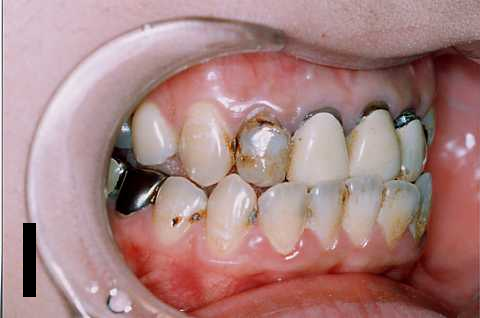

症例 2

| BEFORE | AFTER |

|---|---|